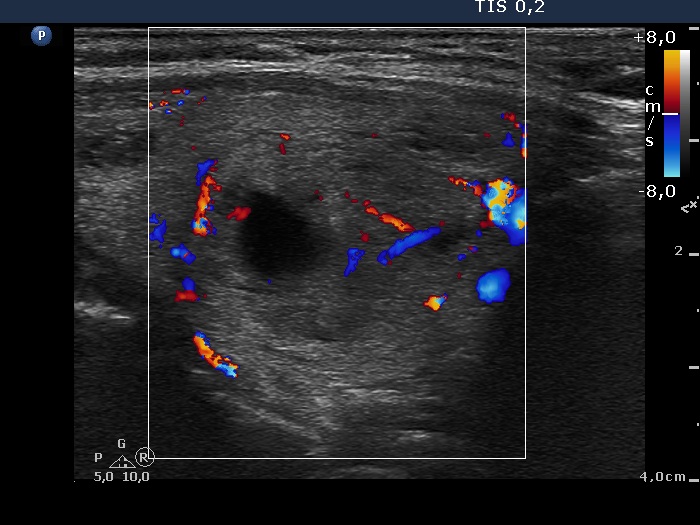

100 consecutive patients with thyroid nodule - Case 35. (ultrasonographic picture 7)

Left lobe, longitudinal scan, color Doppler mode. The lesion displays both perinodular and intranodular blood flow.